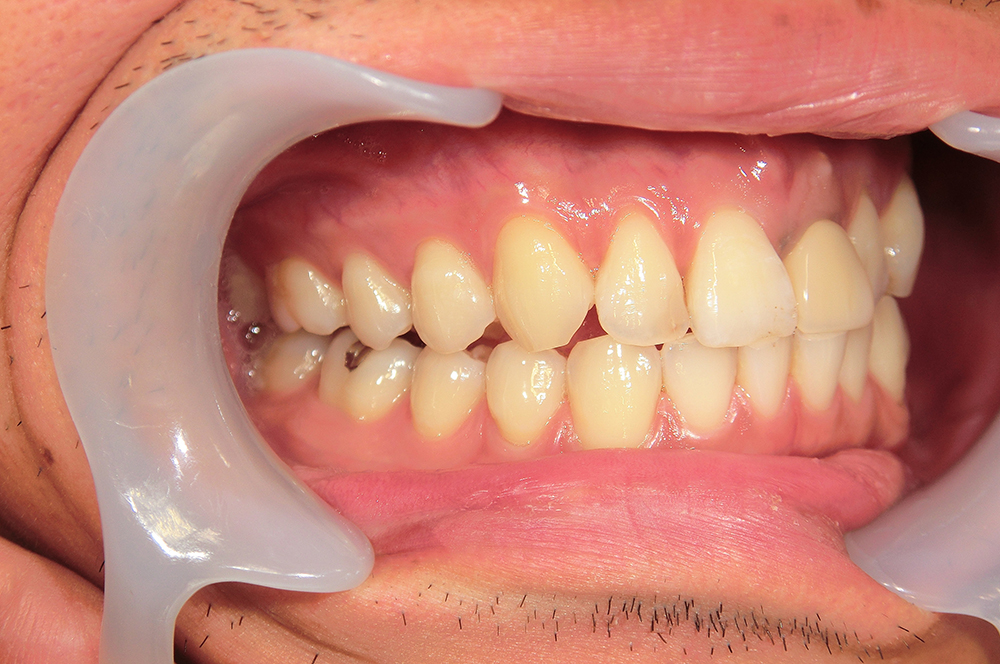

29歳 男性 歯科医療関係者紹介。また、お姉さんが歯科医療関係者。

- 左上1番目の歯が長期にわたり痛く、噛めない。

1本インプラント埋入+再生療法。抜歯即時埋入、即時荷重法⇒抜歯を行い、

同時にインプラント埋入(即時埋入)、そして同時にインプラントへ仮歯を装着(即時荷重)

歯が無い期間なく、社会生活に支障が出ない